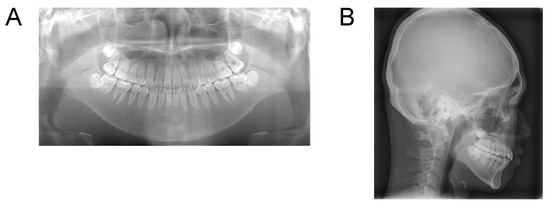

Case 2. Findings from initial examination